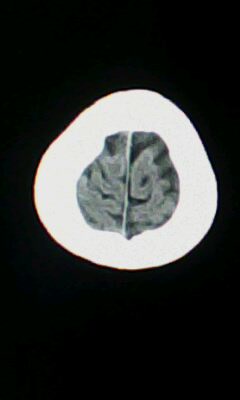

标题: CT25338:女 14岁 3岁时检查为脑积水 现在发育滞后 偶有尿失 [打印本页]

标题: CT25338:女 14岁 3岁时检查为脑积水 现在发育滞后 偶有尿失

脑皮质增厚,发育异常!

左侧灰质异位

建议mri